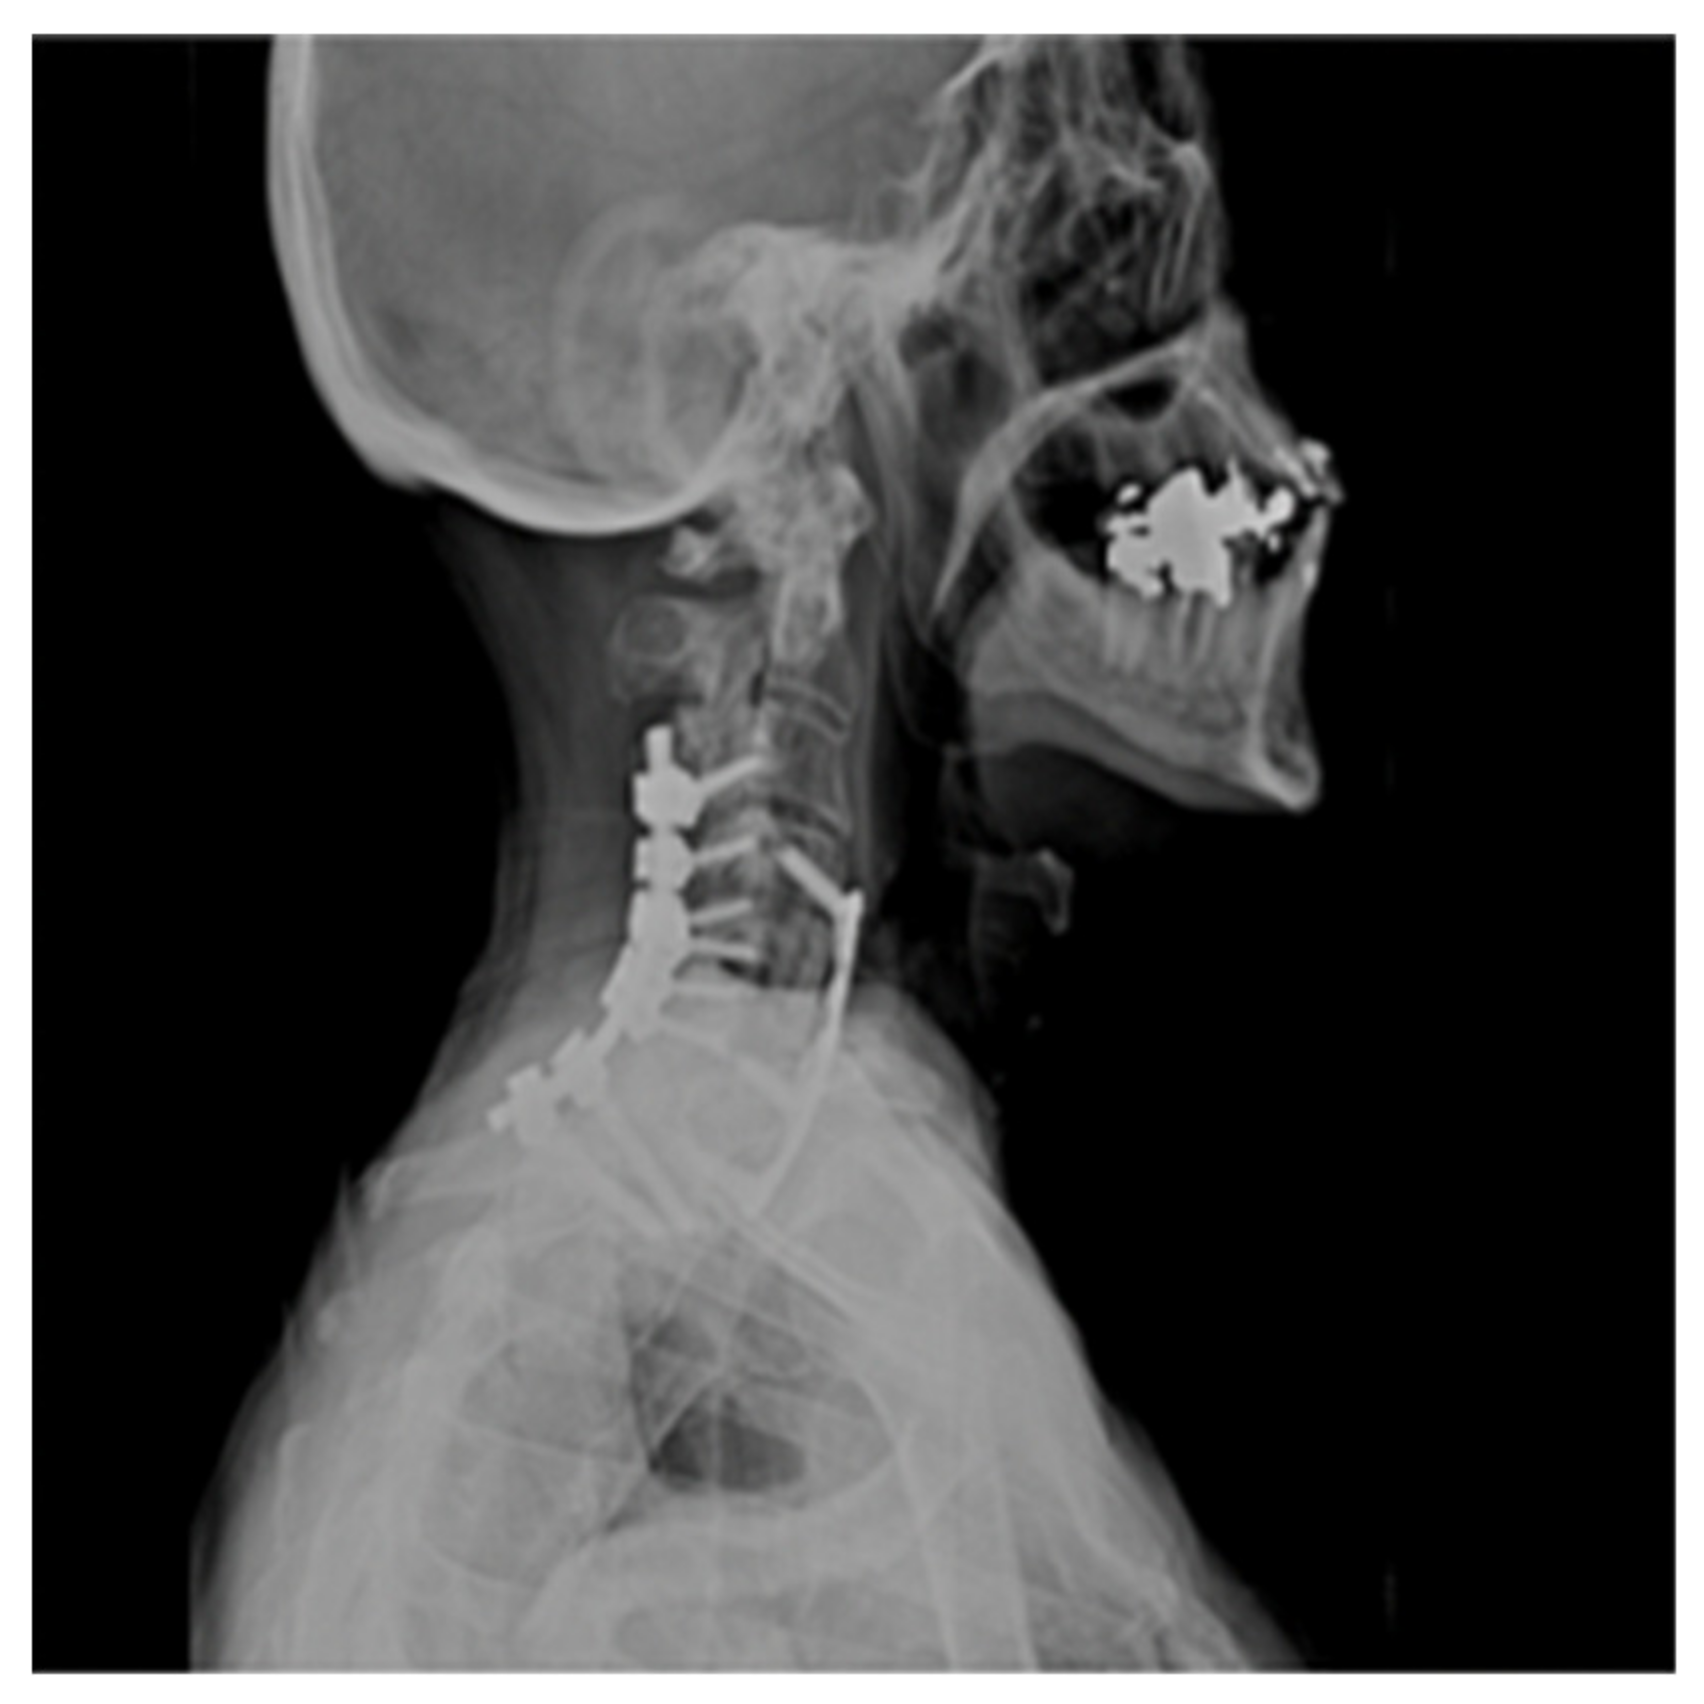

Plain X-rays revealed large anterior osteophytes most prominent from C4–C7 with severe spondylosis. MRI images show spinal cord compression from C4–C7 and myelomalacia at C5–C6, retrolisthesis at C4–C5, and severe multilevel disk degeneration (Figure 1).

Figure 1. Pre-op Sagittal Magnetic Resonance Image (MRI) (Cervical Spine).